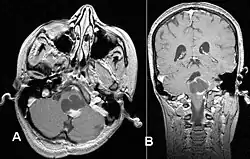

Gwiaździak włosowatokomórkowy (gąbczak, łac. astrocytoma pilocyticum, spongioblastoma, ang. pilocytic astrocytoma) – nowotworowy guz mózgu. Jest guzem o małej złośliwości (I° według WHO). Najczęściej lokalizuje się w półkulach mózgu, podwzgórzu, przednim odcinku drogi wzrokowej (glejak nerwu wzrokowego) i móżdżku. Postępowanie lecznicze zależy od umiejscowienia guza.